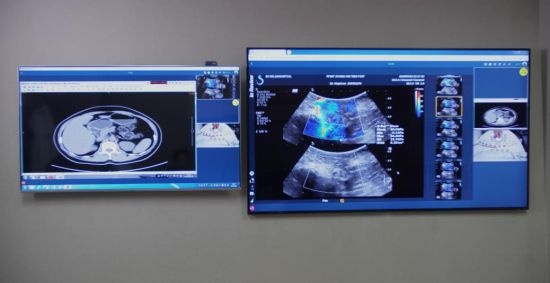

近日,三星QLED 8K電視正式入駐該實驗室,用于醫(yī)療場景的創(chuàng)新應(yīng)用,為廣大醫(yī)療工作者的日常工作帶來更有力的保障。

三星QLED 8K電視正式入駐上海十院5G超聲聯(lián)合創(chuàng)新實驗室

除了5G的“速度”外,終端顯示也很重要。“超

高清”顯示設(shè)備在其中起著不可或缺的作用。“越清楚越好”,郭樂杭強調(diào),超聲等影像

技術(shù)對于圖像質(zhì)量的追求是永無止境的,比起以往的4K顯示器,QLED 8K電視讓畫面更加清晰、明亮,也讓醫(yī)生們能夠為廣大患者做出“一個更好的診斷”。